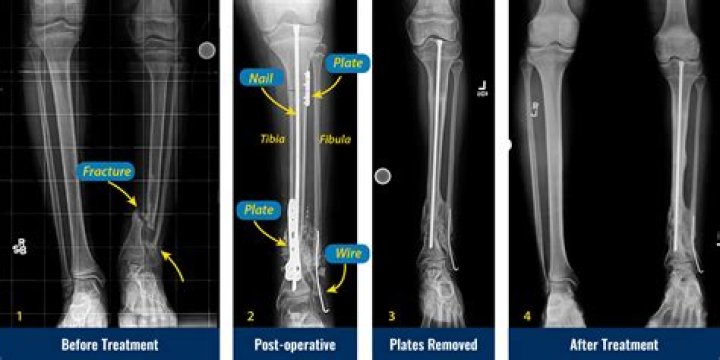

Congenital Pseudoarthrosis Treatment by Paley Cross Union Protocol

Congenital pseudarthrosis of the tibia is a shin bone fracture in children that has not healed. It normally presents before a child turns two years old.

Congenital pseudoarthrosis of the tibia describes abnormal bowing that can progress to a segment of bone loss simulating the appearance of a joint. The condition is usually apparent shortly after birth and is rarely diagnosed after the age of two.

What is tibial pseudarthrosis?

Tibial pseudarthrosis is the name given to a fracture of the tibia (the larger of the two bones in the lower leg) that does not heal correctly.

Can you be born with pseudarthrosis?

Congenital pseudarthrosis of the tibia (CPT) is a rare pathology, which is usually associated with neurofibromatosis type I. The natural history of the disease is extremely unfavorable and once a fracture occurs, there is a little or no tendency for the lesion to heal spontaneously.